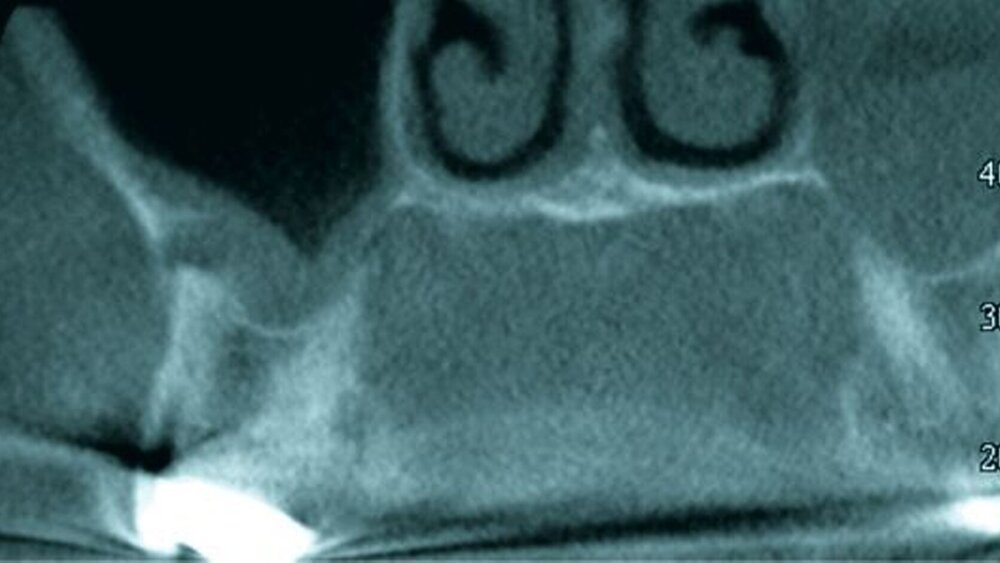

In der weiterführenden Diagnostik mittels digitaler Volumentomografie zeigte sich eine apikale Osteolyse an Zahn 17, die sich in die Kieferhöhle vorwölbte. Daneben fand sich in beiden Kieferhöhlen eine basale Schleimhautschwellung. Da der Patient selbst Mediziner war und sein Erkrankungsbild bereits kannte, wurde er mit der Diagnose eines Quincke-Ödems stationär aufgenommen. Hier erfolgte die intravenöse Gabe von Antihistaminika und Glukokortikoiden. Unter dieser Therapie zeigte sich ein deutlicher Rückgang der Schwellung, so dass die medikamentöse Behandlung ausgeschlichen werden konnte.